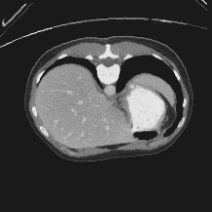

Transformers have made remarkable progress towards modeling long-range dependencies within the medical image analysis domain. However, current transformer-based models suffer from several disadvantages: (1) existing methods fail to capture the important features of the images due to the naive tokenization scheme; (2) the models suffer from information loss because they only consider single-scale feature representations; and (3) the segmentation label maps generated by the models are not accurate enough without considering rich semantic contexts and anatomical textures. In this work, we present CASTformer, a novel type of generative adversarial transformers, for 2D medical image segmentation. First, we take advantage of the pyramid structure to construct multi-scale representations and handle multi-scale variations. We then design a novel class-aware transformer module to better learn the discriminative regions of objects with semantic structures. Lastly, we utilize an adversarial training strategy that boosts segmentation accuracy and correspondingly allows a transformer-based discriminator to capture high-level semantically correlated contents and low-level anatomical features. Our experiments demonstrate that CASTformer dramatically outperforms previous state-of-the-art transformer-based approaches on three benchmarks, obtaining 2.54%-5.88% absolute improvements in Dice over previous models. Further qualitative experiments provide a more detailed picture of the model's inner workings, shed light on the challenges in improved transparency, and demonstrate that transfer learning can greatly improve performance and reduce the size of medical image datasets in training, making CASTformer a strong starting point for downstream medical image analysis tasks.